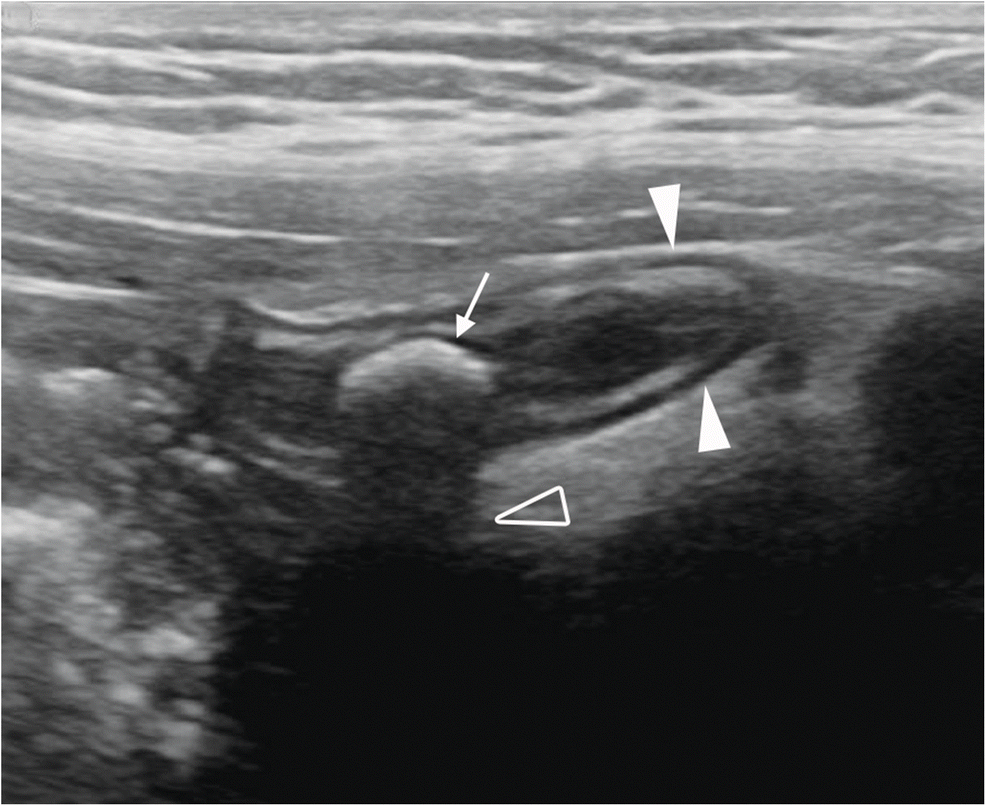

What is the pathology?

Appendicitis with Appendolith